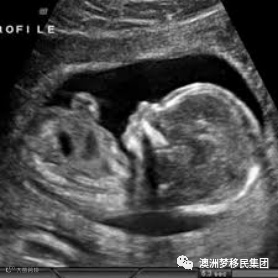

1961年乔治•科索夫(George Kossoff)和戴维•鲁宾逊(David Robinson)在联邦卫生部的超声波研究所制造出了第一台超声波扫描仪。也就是我们照B超的超声波扫描仪,比如用来检查胎儿的情况,如大小,心跳,各器官发育状况等。